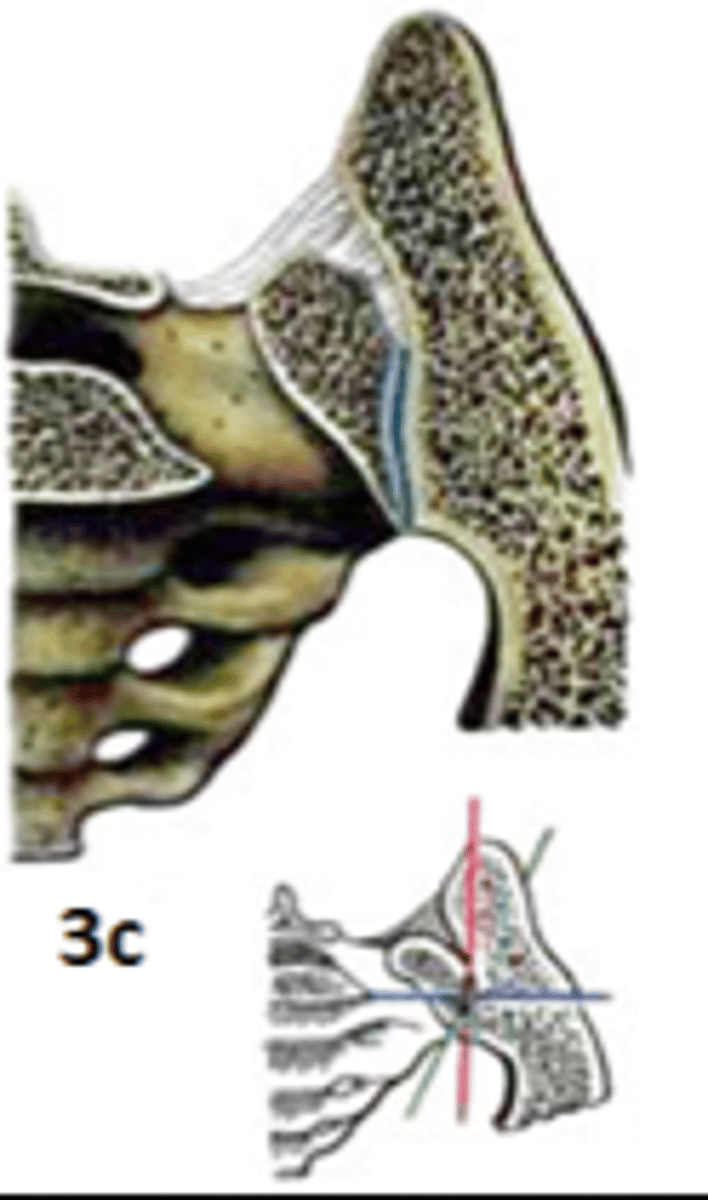

Art. Plana

plakanā locītava (amphiarthrosis- mazkustīga)

Art.sacrococcygea

Art. atlantoaxialis lateralis

Artt. sternocostales 6 pāri

Art. acromioclavicularis

Artt. intercarpales

Artt. carpometacarpales

Artt. intermetacarpales

Art. sacroiliaca

Art. tibiofibularis

Art. calcaneocuboidea

Art. cuneonavicularis

Artt. tarsometatarseae

Artt. intermetatarseae